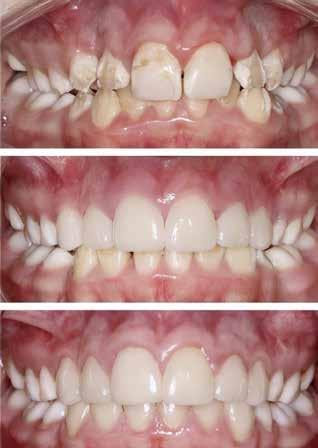

Klinisk undersøgelse viste emaljehypoplasier og hypomineralisering på 1+, +1, 2-, 1-, -1 og -2 (Fig.1). Hun havde Angle klasse II, pladsmangel i begge kæber og agenesi af -5. Der var isninger ved spisning og tandbørstning. Fundene var forenelige

med amelogenesis imperfecta (AI), kombination af hypoplasiog hypomaturationstype. Hypoplastiske områder på incisiver i overkæben blev dækket med komposit som indledende behandling, men da pigen blev ni år, var det tydeligt, at denne behandling ikke havde fungeret som forventet, og der var behov for ny behandling (Fig. 2). Kompositfyldningerne bandt dårligt, var plakretinerende og blev hurtigt misfarvede, hvilket medførte hyppige omlavninger. Hun kradsede sig i tandkødet og pillede ofte med neglene i fyldningskanterne. Patienten havde et stærkt ønske om smertefrihed samt øget holdbarhed og bedre æstetik på restaureringer.

Vurdering af behandling

Behandlingsplan blev udarbejdet i samarbejde mellem specialister i pædodonti, ortodonti, oral rehabilitering, radiologi,

Patienten er syv år

Fig. 1. A-C. Kliniske forhold ved syvårsalderen. Der ses en tynd kant af emalje med hvide opaciteter approksimalt, incisalt og cervikalt samt manglende emalje bukkalt og palatinalt/lingvalt. Primære hjørnetænder har emaljehypoplasi og slitage. Pladsmangel i begge kæber.

Fig. 1. A-C. Clinical situation at 7 years of age. A thin margin of enamel with white opacities on proximal, incisal, and cervical surfaces, with absence of enamel on buccal, palatal and lingual surfaces is seen. Primary canines have enamel hypoplasia and signs of wear. Insufficient space observed in both jaws.

oral kirurgi og oral medicin. Målet var at opnå et funktionelt og æstetisk tandsæt med god holdbarhed på restaureringer. Det var også vigtigt at forebygge negativ påvirkning på pigens psykosociale sundhed på grund af tændernes udseende og funktion. Der var behov for både ortodontisk og protetisk behandling på grund af tandudviklingsforstyrrelsen, agenesi af -5 og pladsmangel i begge kæber. På grund af dårlige erfaringer med komposit og behov for restaurering og omformning af flere tænder anbefalede man, på trods af patientens alder, protetisk behandling fra 4+ til +4. Oprindelig blev det planlagt at lave laminater i glaskeram (litiumdisilikat), men i samråd med tandtekniker valgte man i stedet at fremstille laminater i feldspatkeram, fordi det var ønskeligt at opnå minimal præparation og tynd afslutning gingivalt, og fordi de æstetiske krav var meget høje. Før protetisk behandling kunne gennemføres, skulle

Patienten er ni år

Fig. 2. Kliniske fotografier og panoramarøntgen taget i niårsalderen. A. Der ses hypoplasier på permanente incisiver, hjørnetænder og præmolarer. Misfarvede kompositfyldninger på 1+, 2-, 1-, -1 og -2. B og C. Primære molarer og første permanente molarer har opak emalje med okklusal slitage. D. Panoramarøntgen viser total pladsmangel for hjørnetænder i overkæben og agenesi af -5.

Fig. 2. Clinical photographs and panoramic radiograph, 9 years old. A. Hypoplasia observed on permanent incisors, canines, and premolars. Discoloured composite fillings on 11, 31, 32, 41, and 42. B and C. Primary molars and first permanent molars have opaque enamel with occlusal wear. D. The panoramic radiograph shows lack of space for canines in the maxilla and agenesis of tooth 35.

3+ og +3 fjernes kirurgisk, -05 og 4- ekstraheres på grund af pladsmangel, og tændernes position korrigeres ved hjælp af ortodonti (alignere). Okklusalt på 5+ og +5 anbefalede man komposit til at dække hypoplasier. Der var også behov for protetisk behandling i underkæben på længere sigt.

Præprotetisk behandling gennemført i alderen 9-12 år

Pigen gennemgik omfattende behandling med kirurgisk fjernelse af 3+ og +3 under oral sedering med midazolam mikstur, ekstraktion af -05 og 4- under lattergassedering og præprotetisk ortodontisk behandling i overkæben (Fig. 3). I underkæben var der tandmellemrum på 2-3 mm på hver side efter ekstraktioner, men man vurderede, at der ikke var behov for ortodontisk behandling.

Protetisk behandling

Der blev udført digital scanning for studiemodeller og simulering (mock-up) før præparation, så patienten kunne se og godkende udformningen af laminaterne. Behandling blev iværksat efter justering af mock-up og farvevalg i samråd med tandtekniker.

Efter administration af lokalanalgesi (Septocaine®) blev der præpareret forsigtigt og hovedsagelig i emalje, men enkelte områder med dybe emaljehypoplasier blev udfyldt med ny komposit. Præparationsgrænsen blev lagt i emalje, og kon-

Patienten er 12 år

Fig. 3. A og B. Før og efter ortodontisk behandling med alignere i overkæben ved 12-årsalder. Patienten havde meget god kooperation, og den ortodontiske behandling tog kun et par måneder. C. Panoramarøntgen viser status ved 11,5 års alder efter ekstraktion af 4- og -05 samt kirurgisk fjernelse af 3+ og +3.

Fig. 3. A and B. Before and after orthodontic treatment with aligners in the maxilla at age 12. The patient compliance was excellent, and the orthodontic treatment time was only a few months. C. Panoramic radiograph shows status at 11.5 years of age after extraction of 75 and 44 as well as surgical removal of 13 and 23.

Påsætning af laminater

Fig. 4. A og B. Regio 4+ til +4 efter præparation og før cementering af laminater under anvendelse af kofferdam og retraktionstråd.

Fig. 4. A and B. Teeth 14-24 after preparation and before cementation of ceramic veneers, isolated with rubber dam and retraction cord.

taktpunkter blev bevaret. Aftryk blev taget med Impregum® (3M) og temporære laminater fremstillet i Protemp® (3M) ved hjælp af Exaclear® skinne (GC) og cementeret med Temp Bond® (Kerr). Ved næste seance blev de midlertidige laminater fjernet, de præparerede flader pudset rene med pimpsten og laminater indprøvet efter administration af lokalanalgesi (Septocaine®). Der blev benyttet gingival retraktionstråd og kofferdam (Fig. 4). Laminaterne var forbehandlet med flussyreætsning hos tandtekniker. Efter indprøvning blev keramets indre flader rengjort med fosforsyre, spulet med vand og blæst tørre før silanisering med Bis-Silane® (Bisco). Emaljen blev ætset med fosforsyre i 15 sekunder, skyllet godt med vand og blæst tør med let lufttryk. Bondingsystemet, som blev benyttet, var All-Bond 2® (Bisco), og laminaterne blev cementeret med Variolink Esthetic LC® neutral (Ivoclar) efter producentens anvisning.

Der var behov for meget lokalanalgesi, og effekten blev oplevet som kortvarig, formentlig som følge af patientens tandudviklingsforstyrrelse. Behandlingen var omfattende og tidkrævende for en ung patient. Ydermere var der problemer med at lave holdbare og æstetisk tilfredsstillende midlertidige laminater, hvilket også medførte forværring af isningerne i perioden fra præparation og frem til cementering.

Ved kontrol fire dage efter cementering var patienten yderst tilfreds med behandlingen. Cementoverskud blev fjernet og 5+, +4 og +5 som planlagt forseglet med komposit i okklusale hypoplasier. Dette medførte en lille forøgelse af den okklusale vertikale dimension, som patienten accepterede. Der blev taget aftryk og fremstillet en gennemsigtig aftagelig plade (StaVac®) til overkæben til anvendelse om natten for at retinere det ortodontiske resultat.

Fig. 5. A. Før protetisk behandling (11 år). B. Efter protetisk behandling med laminater regio 4+ til +4 (12 år). C. To år efter cementering af laminater i overkæben (14 år). Patienten har også fået laminater i underkæben (regio 3- til -4).

Fig. 5. A. Before prosthetic treatment (age 11). B. After prosthetic treatment with veneers on teeth 14-24 (age 12). C. Two years after cementation of veneers in the upper jaw (age 14). The patient has also received veneers in the lower jaw (teeth 34-43).

klinisk relevans

For unge patienter med behov for omfattende restaurering er der flere behandlingsmuligheder, som klinikere bør kende til. Protetisk behandling med adhæsiv teknik kan være en god og holdbar løsning på specielle indikationer. Patientens ønsker og motivation må inddrages i behandlingsvalget, da behandlingen er teknikfølsom og tidkrævende. Tidlig protetisk behandling kan give unge patienter forbedret livskvalitet og modvirke udvikling af fremtidig tandlægeskræk og angst.

Da patienten var fyldt 13 år, blev der fremstillet laminater i feldspatkeram regio 3- til -3 og laminat i glaskeram (litiumdisilikat) på -4. Ved kontrol to år efter cementering af laminater i overkæben var patienten stadig godt tilfreds med funktion og æstetik (Fig. 5).

DISKUSSION

Levetiden for kompositfyldninger er generelt kortere hos patienter med AI end hos andre, hvilket medfører hyppige tandlægebesøg og mange fyldningsrevisioner (2). Det var også tilfældet for pigen i denne kasuistik. Kompositfyldningerne var plakretinerende, fyldningskanterne blev hurtigt misfarvede, og patienten kradsede meget i tandkødet og pillede med neglene i fyldningskanterne, hvilket kan have været medvirkende til den korte levetid og de hyppige behov for omlavninger.

Patienter med AI har ofte funktionelle behov for tandbehandling på grund af hypersensitivitet, smerte, fraktur og sli-

tage. Mange er plaget af tændernes udseende og undgår social kontakt, hvilket medfører indskrænkninger i livsførelsen (3). Børn og unge med AI har reduceret oral sundhedsrelateret livskvalitet sammenlignet med børn og unge uden AI, og tidlig protetisk behandling kan forbedre livskvaliteten uden at give patienterne mere frygt og angst for tandbehandling eller negative holdninger til tandbehandling (4,5). Det er påvist, at helkeramiske restaureringer giver god æstetik, god holdbarhed og få komplikationer hos unge patienter med alvorlig AI (6). Pigen i denne kasuistik var plaget af hypersensitivitet i flere tænder og var aldrig tilfreds med de æstetiske resultater, der blev opnået ved hjælp af komposit. Hun var motiveret og klar til at få protetisk behandling. Det var ønskeligt at præparere minimalt på grund af hendes unge alder, den begrænsede mængde emalje og de høje krav til æstetik. Der var også behov for omformning af førstepræmolarer til hjørnetænder. Feldspatkeram er et materiale med vældig god æstetik og kan benyttes i fronten, hvor tyggebelastningen er lille (7). Laminater i feldspatkeram kan afsluttes hvor som helst på tanden, og afslutningen kan være papirtynd. Selvom laminater, der er bondet til hypomineraliseret emalje vil give svagere binding sammenlignet med frisk emalje, kan man alligevel forvente bedre levetid og æstetik end for direkte kompositrestaureringer (8) og mindre behov for omlavning. Det blev derfor vurderet, at protetisk behandling med adhæsiv teknik var det bedste alternativ, idet dette tillod en minimal invasiv behandling for denne pige.

Etiske betragtninger

Patientens motivation, behov, symptomer og kooperationsevne er styrende for behandling, og barnets mening skal tillægges behørig vægt i forhold til dets alder og modenhed (9). Forældre kan også have forskellige meninger og erfaringer, som påvirker, hvad de ønsker for deres børn. Det er vigtigt at individualisere behandlingen, og målet bør være holdbare løsninger og bedst mulig livskvalitet. Dialog med både patient og omsorgspersoner er af stor betydning for god sundhedsforståelse og varetagelse af den unge patient.

KONKLUSION

Tandbehandling af børn og unge med adhæsiv teknik er tidkrævende og teknikfølsom. Den omfattende behandling var krævende for patienten, men heldigvis levede resultatet af

A B C

behandlingen op til hendes forventninger. Tænderne blev hen ad vejen symptomfrie, og hendes livskvalitet steg betragteligt efter behandlingen. I nogle tilfælde er der stærk indikation for tidlig protetisk behandling hos børn og unge, og dette bør da gennemføres. Det er vigtigt ikke at påføre unge patienter negative erfaringer, og anvendelse af medikamentel sedering, lattergassedering og i særlige tilfælde endog generel anæstesi bør overvejes.

TAK

Tak til Afdeling for oral protetik, IKO, UiO, for gode diskussioner og forslag til behandlingsplan. Tak til Afdeling for oral kirurgi og oral medicin, IKO, UiO, hvor den kirurgiske behandling blev udført. Tak til Afdeling for ortodonti, IKO, UiO, for godt samarbejde og for kliniske fotografier og til Afdeling for kæbeog ansigtsradiologi, IKO, UiO, for billeddiagnostik. En stor tak rettes også til patient og forældre for samtykke til publicering.

ABSTRACT (ENGLISH)

PROSTHETIC TREATMENT WITH ADHESIVE TECHNIQUE – AN OPTION FOR YOUNG PATIENTS?

BACKGROUND – This case report describes a patient for whom prosthetic treatment was chosen at a young age.

CASE STUDY – The girl had pain from her teeth and extensive need for treatment due to a dental developmental disorder. Several attempts with composite restorations were unsuccessful. Feldspatic ceramic veneers were chosen for minimal removal of tooth substance and to increase the durability of

LITTERATUR

1. Sveinsdottir EG, Espelid I. Dentale utviklingsforstyrrelser – kliniske utfordringer i diagnostikk og behandling. I: Holmstrup P, ed. Aktuel Nordisk Odontologi. Oslo: Universitetsforlaget, 2016;41: 126-45.

2. Pousette Lundgren G, Dahllöf G. Outcome of restorative treatment in young patients with amelogenesis imperfecta. a cross-sectional, retrospective study. J Dent 2014;42:1382-9.

3. Appelstrand SB, Robertson A, Sabel N. Patient-reported outcome

measures in individuals with amelogenesis imperfecta: a systematic review. Eur Arch Paediatr Dent 2022;23:885-95.

4. Rodd HD, Abdul-Karim A, Yesudian G et al. Seeking children’s perspectives in the management of visible enamel defects. Int J Paediatr Dent 2011;21:89-95.

5. Das R, Børstad E, Feuerheim A et al. Tidlig kroneterapi utført hos ungdommer med alvorlig amelogenesis imperfecta forbedrer livsutfoldelsen. Nor Tannlegeforen Tid 2022;132:336-42.

restorations as well as to improve aesthetics. The patient's motivation, opinions, and ability to cooperate were important for the choice of treatment as the treatment was timeconsuming and at times exhausting for the young girl.

CONCLUSION – The result was considered successful and led to an improved quality of life. Prosthetic treatment with adhesive technique can be an effective option for young patients hitting the criteria for use.

6. Pousette Lundgren G, Vestlund GM, Dahllöf G, et al. Crown therapy in young individuals with amelogenesis imperfecta: Long term follow-up of a randomized controlled trial. J Dent 2018;76:102-8.

7. Johansson C, Vult von Steyern P. Porslin och glaskeramer – våra mest estetiska material. Tandlægebladet 2019;123:22-7.

8. Ohrvik HG, Hjortsjö C. Retrospective study of patients with amelogenesis imperfecta treated with different bonded restoration

techniques. Clin Exp Dent Res 2020;6:16-23.

9. UNITED NATIONS. FNs konvensjon om barnets rettigheter. (Set 2024 februar). Tilgængelig fra: URL: https://fn.no/avtaler/menneskerettigheter/barnekonvensjonen

ABSTRACT

BAGGRUND – Patienter med amelogenesis imperfecta har oftest et livslangt behandlingsbehov, fordi insufficient mineraliseret emalje fører til fraktur, slid, symptomer, caries, begrænset holdbarhed af restaureringer og insufficient æstetik. Det er derfor vigtigt, at behandlingsvalg relateres til patientens alder og behov, samt at en noninvasiv tilgang tilstræbes.

PATIENTTILFÆLDE – I denne artikel gennemgås behandlingen af en 16-årig dreng med æstetiske problemer i fronten, hvor okklusalt slid endnu ikke er behandlingskrævende. Behandlingsprincippet tager udgangspunkt i patientens unge alder og udføres derfor med direkte plast. De kliniske procedurer bliver udførligt beskrevet undervejs.

KONKLUSION – Noninvasiv adhæsiv teknik kunne løse patientens æstetiske behov, og efter 10 år var der fortsat god holdbarhed af plasten. Til sidst diskuteres behandling af forskellige aldersgrupper kort, herunder valg af forskellige materialer samt holdbarhed.

EMNEORD Amelogenesis imperfecta | restorative treatment | adhesives | composite resin

Adhæsiv behandling af ung patient med amelogenesis imperfecta

ULLA PALLESEN, overtandlæge, Odontologisk Institut, Københavns Universitet, Danmark

Accepteret til publikation den 21. marts 2024 Tandlægebladet 2024;128:764-9

IDENNE ARTIKEL FOKUSERES PÅ BEHANDLING AF EN 16-ÅRIG DRENG MED ØNSKE OM FORBEDRET ÆSTETIK, hvor behandlingsvalget baseres på biologiske hensyn relateret til patientens alder, behov og emaljedefekter. Hos en 16-årig, hvor tænderne skal holde længe, tages specielt hensyn til pulpa, gingiva og bevarelse af tandsubstans ved at anvende noninvasiv teknik med direkte plast uden præparation af tænder. Der fokuseres på optimal mundhygiejne og anvendelse af restaurerende teknik, hvor skånsom behandling prioriteres umiddelbart, men også fremadrettet over et livslangt forløb med kommende omlavninger (1).

AMELOGENESIS IMPERFECTA

• Amelogenesis imperfecta (AI) er en sjælden nedarvet sygdom og den hyppigst forekommende genetisk betingede afvigelse i tanddannelsen (2-4).

• Når AI er til stede, omfatter den alle tænder i både det primære og permanente tandsæt og er oftest mest udtalt i de permanente tænder (2).

• AI inddeles ofte i den hypoplastiske type (kvantitativ) og i den hypomineraliserede type (kvalitativ, hypocalcificeret/hypomatureret) (2,4).

Korrespondanceansvarlig forfatter: ULLA PALLESEN ul@sund.ku.dk

• Symptomer ved AI er karakteriseret ved hypersensitivitet, nedsat tyggefunktion, slid, caries, misfarvning, ændret morfologi og evt. åbent bid i tandsættet (2,4).

Før og efter fjernelse af gammel plast

Fig. 1. A. Før behandling af 16-årig dreng med behov for æstetisk behandling. Den gamle plastbehandling bærer præg af små frakturer, kant- og corpusmisfarvning og manglende afdækning af alle flader (klinisk mere udtalt end gengivet på fotoet). B. Efter forsigtig fjernelse af gammel plast fremgår det, at 14 og 13 er kraftigt misfarvet.

Fig. 1. A. Before treatment of 16-year-old boy in need of aesthetic treatment. The old resin restorations are marked by small fractures, marginal – and corpus discoloration and do not cover all surfaces (clinically more pronounced than reproduced in the photo). B. After careful removal of old composite resin material, it appears that 14 and 13 are severely discolored.

PATIENTTILFÆLDE

Introduktion

En 16-årig dreng med AI var som følge af diagnosen blevet fulgt tæt i den kommunale tandpleje i sin opvækst, hvor æstetisk behandling med plast var udført og repareret flere gange. Da patienten blev 16 år og mere bevidst om sit udseende, kom der fra familien et ønske om at få æstetikken væsentligt forbedret (Fig. 1A), og han blev henvist til privat praksis for behandling hos artiklens forfatter. Moderen med samme diagnose, som selv havde været gennem en stor restaurerende behandling med fuldkroner på alle tænder, var indstillet på, at der skulle findes en mere skånsom løsning til sønnen, og at behandling med fuldkroner skulle udsættes længst muligt. Samtidig var både mor og søn bevidste om, at æstetikken skulle være høj, og at behandlingen skulle have god holdbarhed. Patienten var sund og rask, havde god mundhygiejne og ellers sunde orale forhold. Ud fra de tænder, der ikke var dækket med plast, blev AI-typen vurderet til at være den hypomineraliserede (kvalitativ defekt, hypomatureret), fordi tænderne havde normal størrelse, der var begyndende nedbrud af emaljen okklusalt (se Fig. 5B), og emaljen var opak hvidlig eller gult/gråligt misfarvet (se Fig. 6) (4). Den eksisterende plastbehandling på overkæbefortænder, hjørnetænder og præmolarer var let insufficiente flere steder (kantmisfarvning, gennemskin af misfarvning og dækkede ikke facialfladerne helt), hvilket

fremgår af Fig. 1A, hvor det dog kan nævnes, at æstetikken var mindre god end gengivet på det kliniske foto, hvilket ofte er tilfældet på billeder.

På det givne tidspunkt var der ikke indikation for behandling okklusalt, fordi emaljen persisterede mange steder (begrænset slid) og der ikke var symptomer fra tænderne. Heller ikke misfarvning af underkæbefortænderne syntes at være et problem for patienten. Derimod var behovet for forbedring af æstetikken i overkæbefronten og ønsket om mere holdbare restaureringer forståeligt, og der var således indikation for behandling af facialflader på præmolarer, hjørnetænder og incisiver i overkæben. Med udgangspunkt i patientens unge alder blev det besluttet at udføre behandlingen noninvasivt med direkte plast.

BAGGRUND – Denne kasuistik beskriver en patient, hvor der blev valgt protetisk behandling i ung alder.

PATIENTTILFÆLDE – En niårig pige havde stort behandlingsbehov og smerter fra tænderne på grund af tandudviklingsforstyrrelse. Der var flere gange forsøgt restaurering med komposit, som ikke fungerede. Laminater i feldspatkeram blev valgt for at fjerne mindst mulig tandsubstans, øge holdbarheden på restaureringerne og forbedre æstetikken. Patientens motivation, meninger og kooperationsevne var vigtige for behandlingsvalget, da behandlingen var tidkrævende og til tider udmattende for en ung patient.

KONKLUSION – Resultatet var vellykket og medførte forbedret livskvalitet. Protetisk behandling med adhæsiv teknik kan være et godt behandlingsalternativ for børn og unge på ret indikation.

EMNEORD Adhesives | amelogenesis imperfecta | ceramics | pediatric dentistry | quality of life

Protetisk behandling med adhæsiv teknik –et alternativ i ung alder?